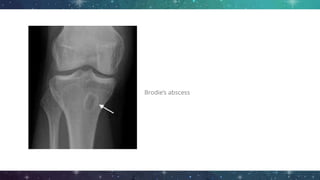

Imaging

● Plain film radiography

○ Extend at least 1cm/ compromise 30 -

50% of bone mineral

○ Bone destruction may not appear until

approximately 2 weeks after onset

○ Osteolysis, periosteal reaction and

sequestra

○ Brodie’s abscess

Brodie’s abscess